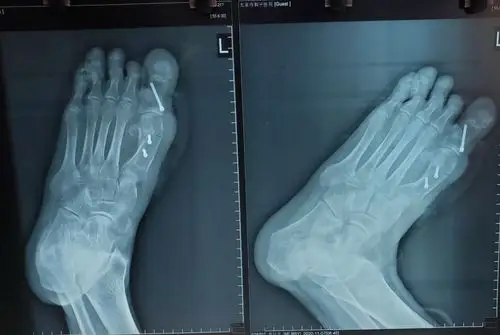

广济手足外科医院近期病例分享之:拇外翻

江西南昌大脚骨手术案例做完当天就能回家又好看又快

陈圣英分析拇外翻矫正削骨不是关键矫正才是关键

大脚骨拇外翻矫形手术